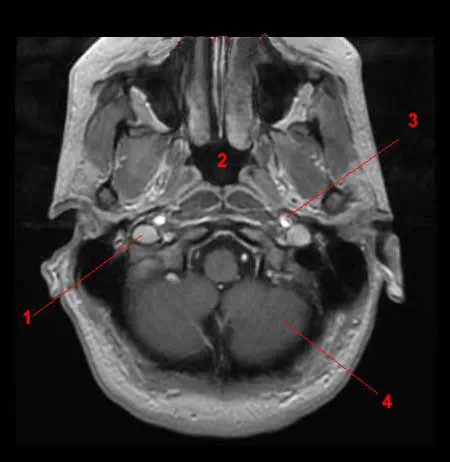

图7 颈内静脉和椎静脉(磁共振断面)

1.颈内动脉;2.颈静脉球;3.乙状窦;4.小脑。